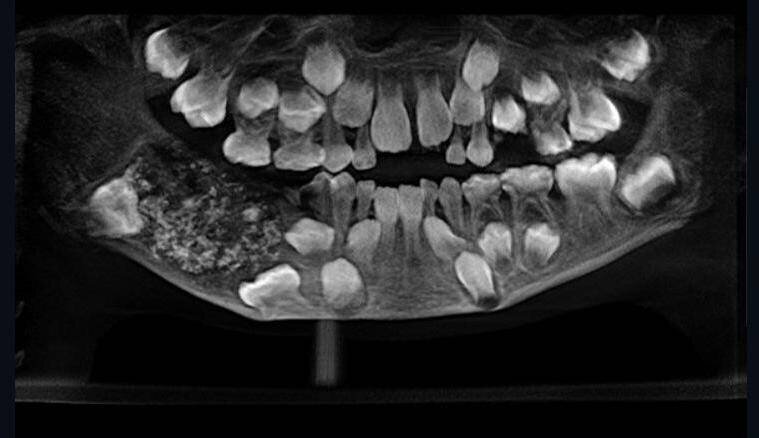

Стоматологический колледж Saveetha Большая лёгкаяконструкция с сотнями зубов видна в левом нижнем углу этой рентгенограммы. Врачи удалили его и разрезали, чтобы найти 526 зубов.

Согласно The Independent , врачи впервые обнаружили большую твердую конструкцию, которая весила почти полфунта в челюсти Равиндраната. Они успешно удалили этот странный органический объект, который вызывал у мальчика такой дискомфорт, и разрезали его, чтобы осмотреть его содержимое.

То, что они нашли, было шокирующим ассортиментом зубов размером от 1 мм до 15 мм. Это были не просто фрагменты, так как каждый зуб имел «коронку, покрытую эмалью и структуру, похожую на корень».